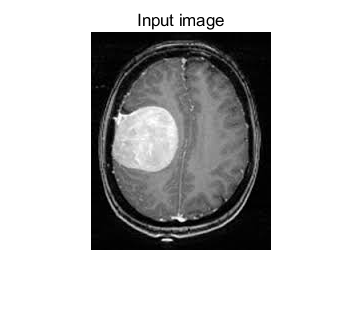

大脑肿瘤(如胶质瘤、脑膜瘤)的早期精准识别是临床诊断与治疗方案制定的核心前提,而磁共振成像(MRI)凭借高软组织分辨率、无辐射损伤的优势,成为大脑肿瘤临床检测的首选影像学手段。然而,原始大脑 MRI 图像常存在噪声干扰(如设备电子噪声、生理运动伪影)、组织边界模糊(肿瘤与正常脑组织灰度差异小)、伪影叠加(如磁化率伪影、血管搏动伪影)三大问题,导致传统视觉诊断或简单阈值分割方法的识别精度低、漏诊 / 误诊率高。

各向异性扩散滤波器(Anisotropic Diffusion Filter, ADF)作为一种自适应图像增强技术,可在保留图像边缘细节的同时抑制噪声—— 其核心优势在于:根据图像局部梯度信息动态调整扩散强度,在平坦区域(如正常脑组织内部)增强扩散以降噪,在边缘区域(如肿瘤与正常组织交界)减弱扩散以保留边界特征。将 ADF 与深度学习识别模型结合,构建 “预处理 - 特征提取 - 肿瘤定位 - 分类” 的完整技术流程,可有效提升大脑 MRI 图像中肿瘤的识别精度与临床实用性,为神经外科医生提供可靠的辅助诊断工具。